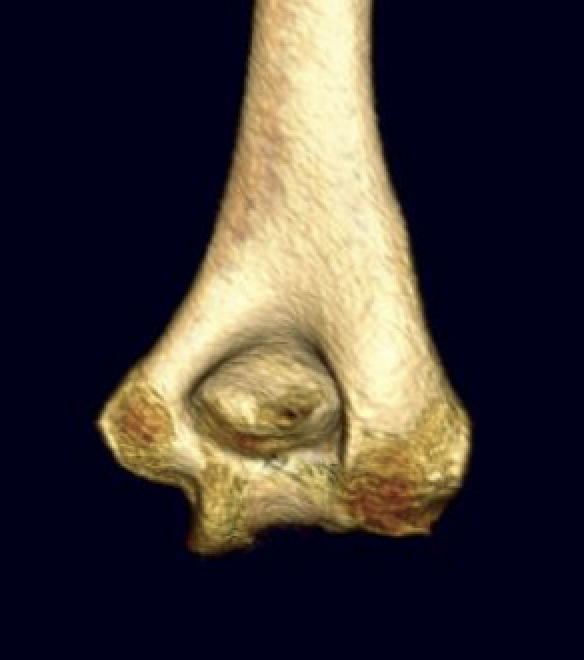

OTA / AO Classification

Type A: Extra-articular fracture

Type B: Partial articular fractures

Lateral condyle Medial condyle

Type C: Complete articular fractures

CT scan